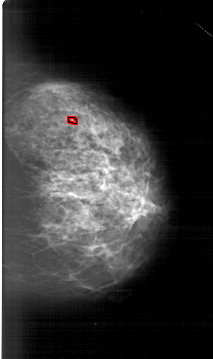

A_1374_1.RIGHT_MLO

RIGHT_MLO LINES 5641 PIXELS_PER_LINE 3901 BITS_PER_PIXEL 12 RESOLUTION 43.5 OVERLAY

FILE: A_1374_1.RIGHT_MLO.OVERLAY

TOTAL_ABNORMALITIES 1

ABNORMALITY 1

LESION_TYPE CALCIFICATION TYPE PLEOMORPHIC DISTRIBUTION CLUSTERED

ASSESSMENT 4

SUBTLETY 2

PATHOLOGY BENIGN

TOTAL_OUTLINES 1

BOUNDARY